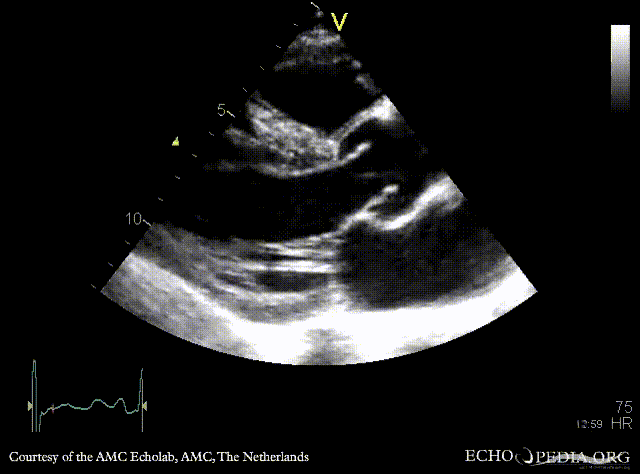

Severe aortic regurgitation

PLAX: aortic valve vegetation, dilated left ventricle PLAX: aortic valve vegetation